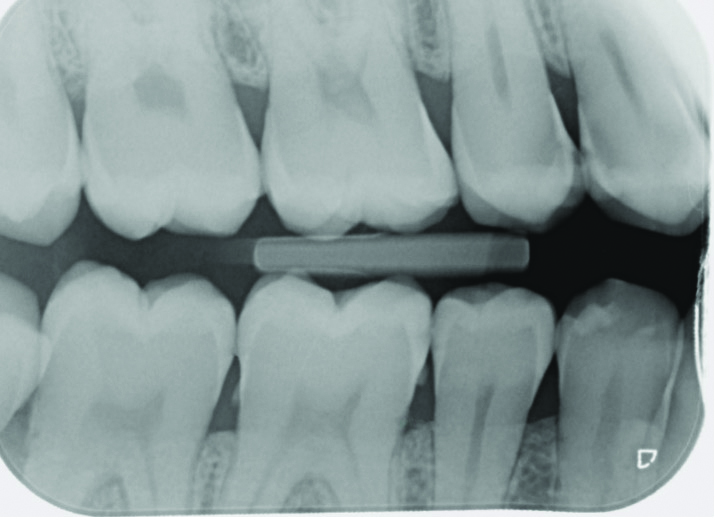

Machine learning (ML): ML refers to a class of AI algorithms that analyze large datasets to identify patterns, make predictions, and improve decision-making. In dental education, ML assists in curriculum design by personalizing learning pathways based on student performance. Additionally, ML models are instrumental in analyzing radiographic images, detecting pathologies, and predicting patient outcomes (Figure 1 and Figure 2).

Fig 1. On a conventional dental radiograph, areas of concern, in this case proximal decay, can be difficult for the patient to see on the black and

white image.

Figure 1